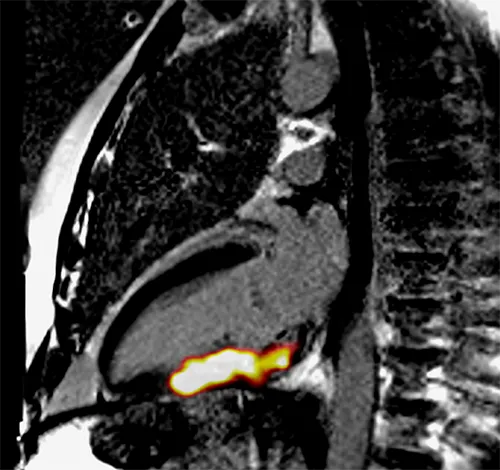

PET-MR image of the heart in 2-chamber & short axis views. The bright yellow-orange region is where 68-Ga-FAPI is taken up in active scar tissue which correlates to damage from a recent heart attack. This tells us that 68-Ga-FAPI PET identifies tissue damage very well & when combined with anatomical imaging, is a promising method to help us learn more about human cardiovascular scarring.

Edinburgh Imaging & NHS radio-pharmacy collaborated successfully to produce the first ever Gallium radiotracer cardiac images in patients who recently suffered heart attacks.

To the best of the team’s knowledge, their initial scans obtained in patients who had recently suffered heart attacks were the first 68Gallium (68Ga)-FAPI PET-MR performed in patients without cancer.

The team secured ethical, ARSAC & R&D approval to scan a larger number of patients & healthy volunteers to learn more about the scarring process in the heart & blood vessels following a heart attack.

The FAPI fibrosis study continues to recruit patients following myocardial infarction to allow the team to discover more about the timing & pattern of the healing response within the myocardium & vasculature in this condition.

The team are investigating how to maximise the number of scans it is possible to perform with each batch of 68Ga-FAPI which makes this exciting technology more useful clinically & may help reduce the small radiation dose it entails.